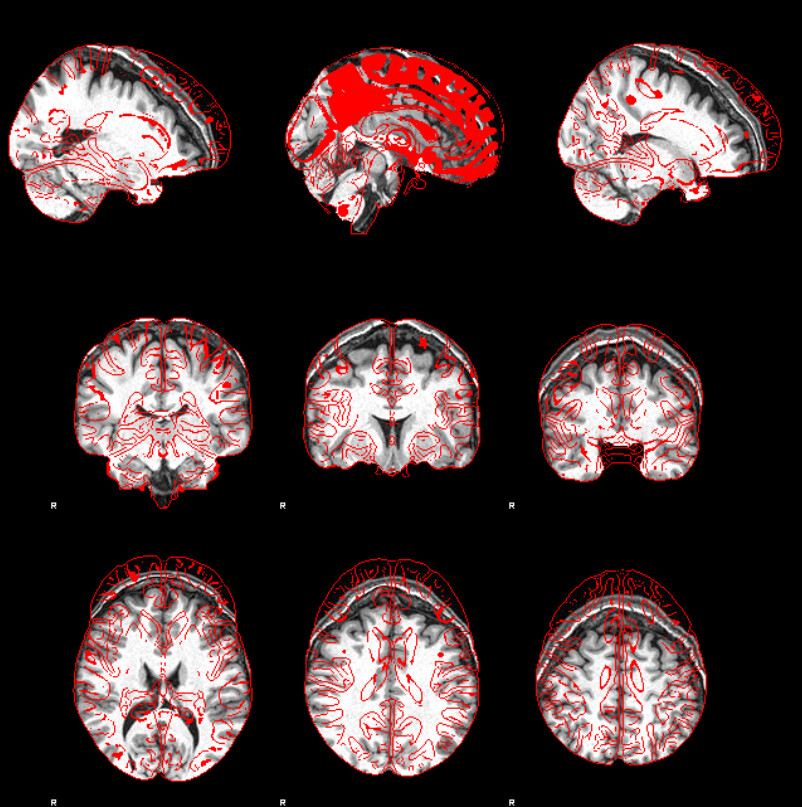

I’m using xcp_d for post-process the output from fmriprep. I found misalignment between t1w and atlas almost all the subjects, similar to the case here but with worse result:

Screenshots / relevant information: